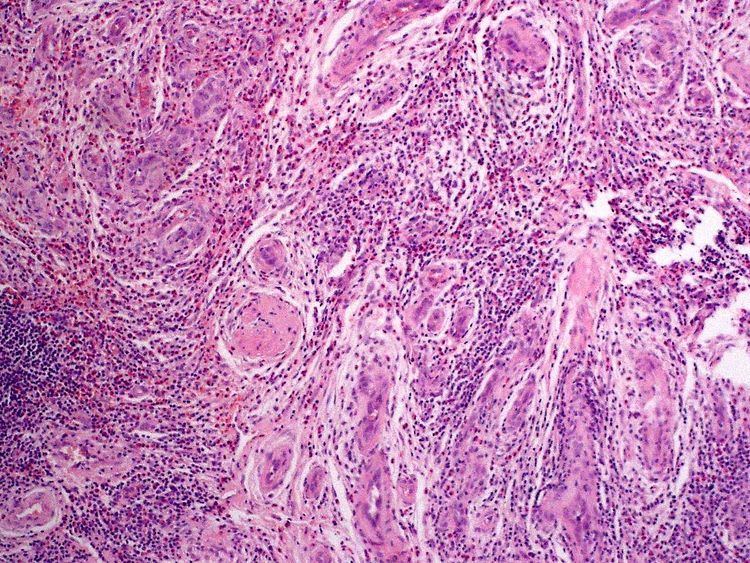

Angiolymphoid hyperplasia with eosinophilia (also known as: "Epithelioid hemangioma," "Histiocytoid hemangioma," "Inflammatory angiomatous nodule," "Intravenous atypical vascular proliferation," "Papular angioplasia," "Inflammatory arteriovenous hemangioma," and "Pseudopyogenic granuloma") usually presents with pink to red-brown, dome-shaped, dermal papules or nodules of the head or neck, especially about the ears and on the scalp.